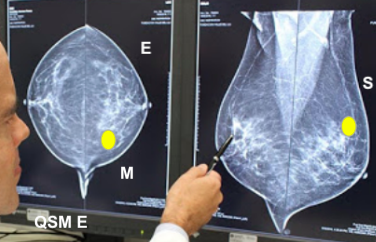

Dê a localização do tumor

Quadrante superior medial esquerdo